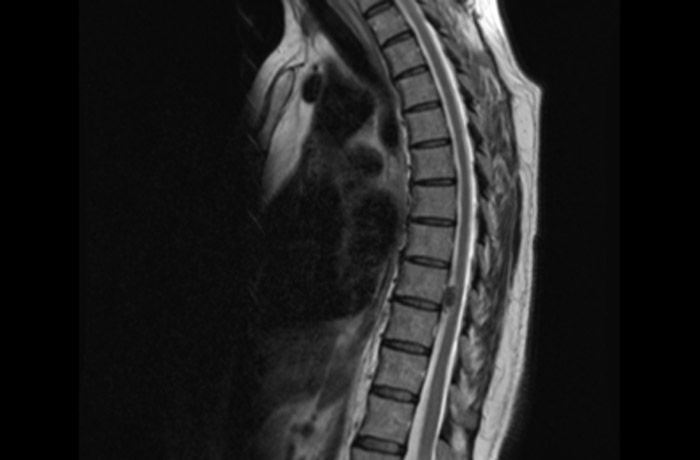

МРТ грудного отдела позвоночника

Современная магнитно-резонансная томография считается самым точным методом диагностики любого участка организма. МРТ грудного отдела позвоночника — возможность детального изучения мягких тканей, костных структур и кровеносных сосудов центральной части позвоночного столба. Томография способна визуализировать не только поверхностные ткани позвоночника, но и его внутренние ткани, включая хрящевые образования и нервные волокна.